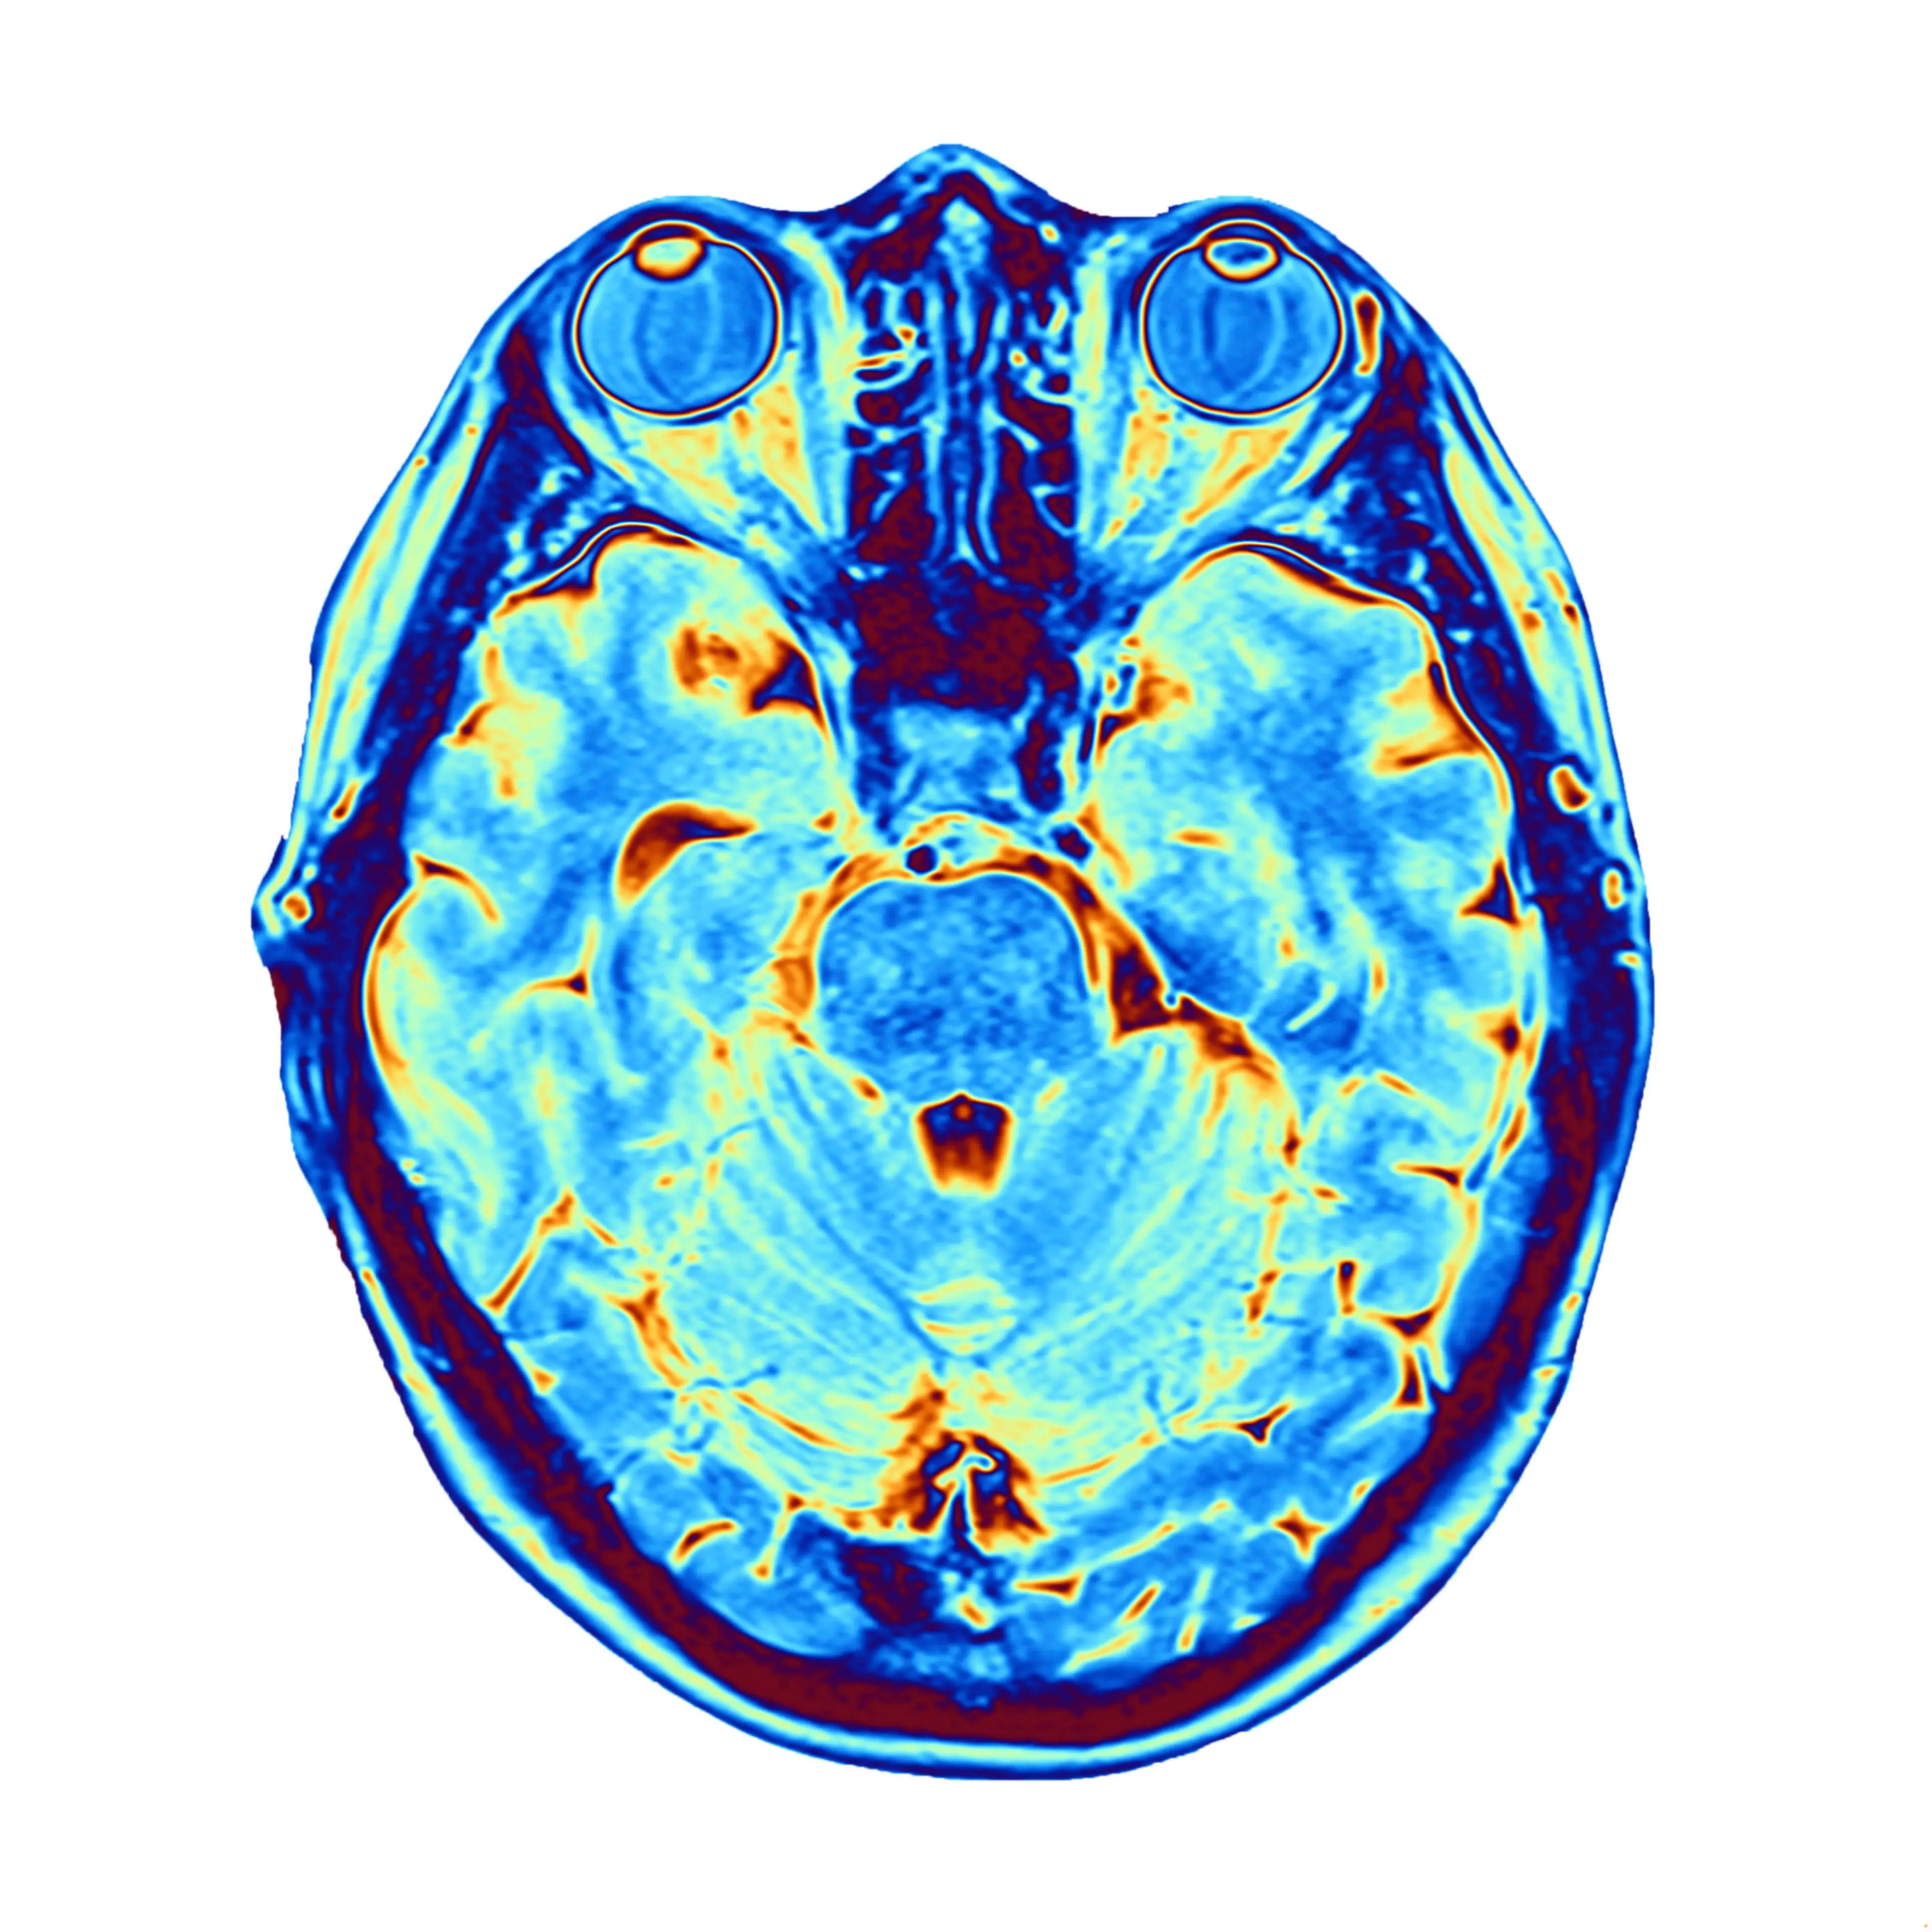

Dr Zemmar explained that more studies would need to be conducted, adding that conclusions cannot be drawn from just one.

"I never felt comfortable to report one case," he said.

However, one study from 2013 also offered interesting findings. In the study, US scientists looked at brainwave activity in healthy rats at the point of death, until 30 seconds after death.

Dr Zemmar described the similarities between his study and the research conducted in 2013 as 'astonishing'.